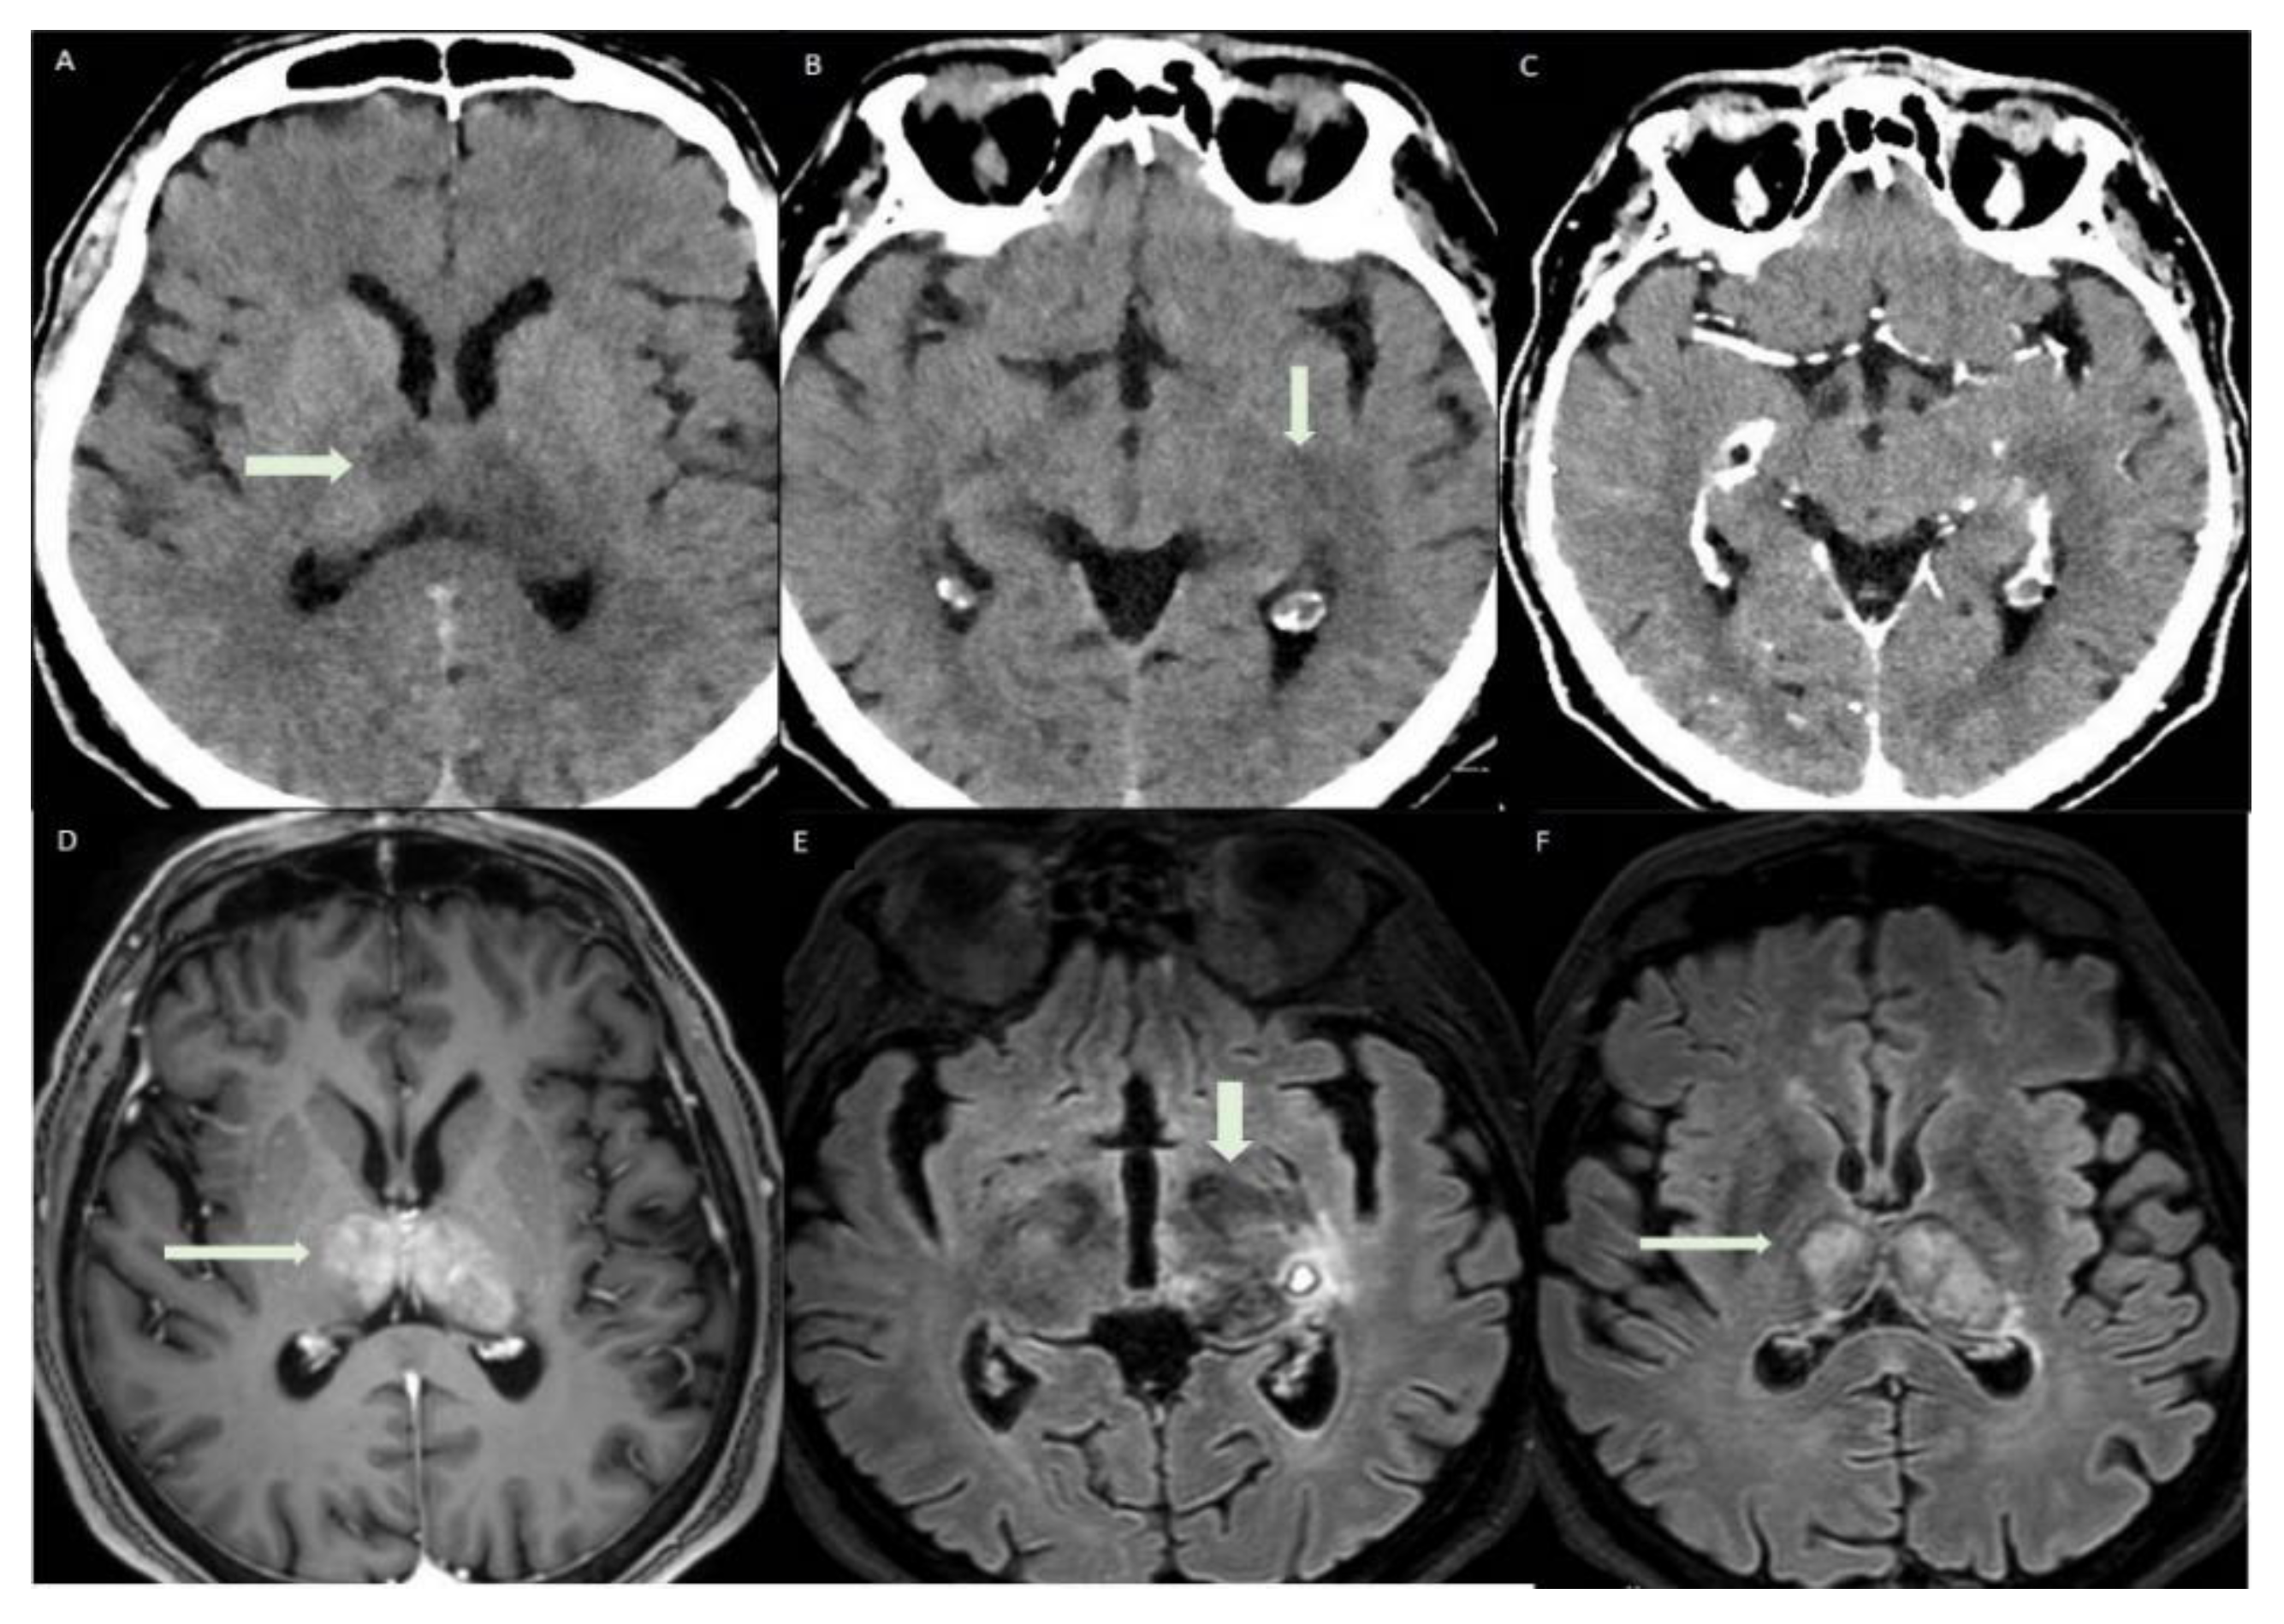

A CT with use of a medium contrast was performed the following day to better appreciate the vascular extension of the thrombosis. In the figure, axial CT images show hypodense areas in thalami and left parahippocampal region (short arrow, ischemic stroke lesions) and spontaneously hyperdense focus in left parahippocampal region (long arrow). This last was interpreted as a focal hemorrhagic transformation of the stroke. CVT in COVID-19 disease has been associated with a strong activation of the inflammatory chain. Specifically, it has been proven the implication of neutrophil extracellular traps (NETs), impaired systemic microcirculatory function, downregulation of natural anticoagulation phenomena and vascular endothelial dysfunction. Alveolar capillary microthrombi from COVID-19-induced immunothrombosis have been also described [3]. Other studies have reported CVT after vaccination against COVID-19 [6]. Thrombotic thrombocytopenia and cerebral venous sinus thrombosis have been observed in patients after receiving the adenovirus-based vaccine (AstraZeneca) and after the first dose of the mRNA-based vaccine, as in our case. Of note, a pathological mechanism which causes CVT in these cases has been postulated, known as “vaccine-induced immune thrombotic thrombocytopenia” (VITT) [7]. Low platelet count and high D-dimer values, as in our case, can assist the diagnosis of VITT after vaccination [8].